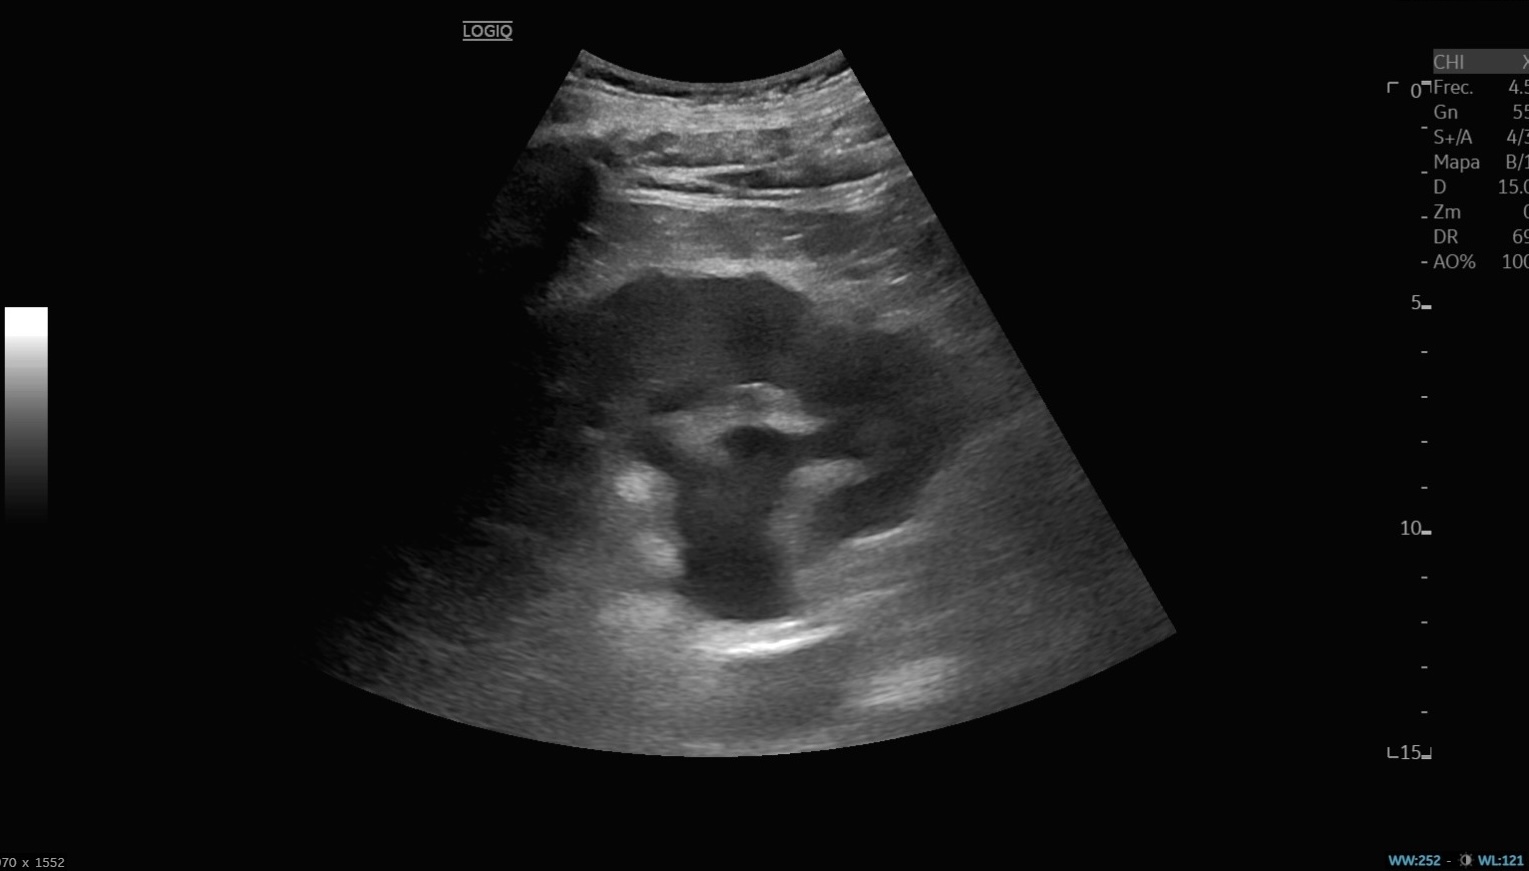

Ecografía abdominal: vejiga hiperdistendida con unos 3000 ml de orina y hidronefrosis bilateral moderada-severa, sin lesiones intravesicales ni causa obstructiva aparente. Analítica: anemia microcítica (Hb 9 g/dl), insuficiencia renal aguda grave (urea 409, creatinina 14,2), acidosis metabólica (pH 7,26; HCO₃ 6,3), PCR 19,7. Sedimento urinario positivo para infección.

Por el cuadro constitucional y vómitos, la primera sospecha fue neoplasia maligna. Sin embargo, la ecografía reveló retención urinaria masiva con afectación pielocalicial bilateral, orientando el diagnóstico hacia insuficiencia renal aguda obstructiva.